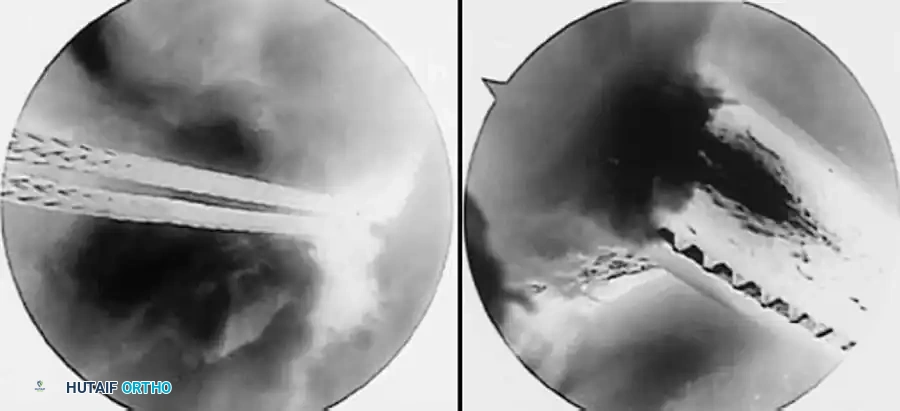

A B

C D

Fig. 48-19 Two-portal technique for bucket-handle tears of lateral meniscus. A, Displaced bucket-handle tear of lateral meniscus probed. B, After reduction of displaced bucket-handle tear, posterior attachment is partially released with scissors. C, Anterior attachment is released with scissors. D, Tenuous remaining posterior attachment is avulsed with grasper and extracted. probe passes into the inferior tear, but not through to the superior surface of the meniscus. Vigorous attempts to hook the probe into an unseen inferior tear should be avoided for danger of extending the tear. If such a tear exists, gentle probing can make the inner border of the meniscus buckle and evert (see Fig. 48-18B). Stable peripheral one-third tears in relatively healthy menisci should be treated by abrasion of the tear site and meniscal synovial tissue to stimulate healing, preserving meniscal function. If stability is in question, suturing may be indicated for most medial meniscal tears (see “Arthroscopic Surgery of the Meniscus” earlier).